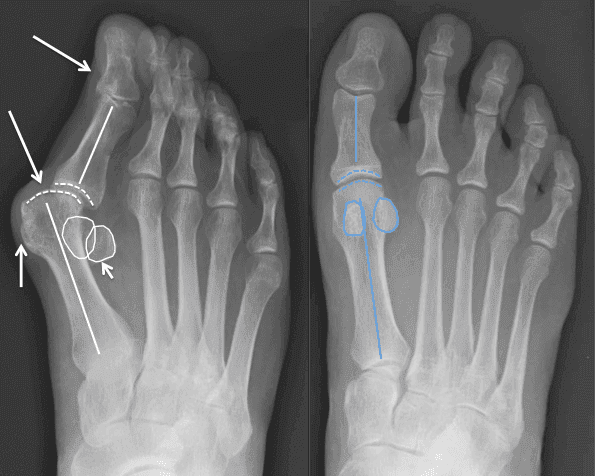

A oto wyniki Artisan po 10 dniach:

Damian: "Miałem problemy związane ze stopą. Niczego nie brałem ... Poszedłem do specjalisty, stosowałem maści i środki ludowe... Nic nie pomogło. Zaufałem Andrzejowi, wziąłem udział w eksperymencie. Po 2 tygodniach po problemie nie było śladu! Oto mój wynik. Dziękuję Andrzejowi".